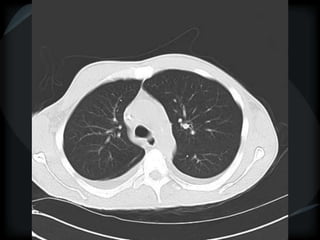

Bronchiectasis

Vessel at wall of cyst – signet ring

Cyst stacked in tubular orientation

Cyst stacked in branching pattern

Dilated, irregular, thickened airways

Mucus-filled airways

Diameter of peripheral airway to accompanying

artery = >1

● HGG ● CD

● ABPA ● tracheobronchomegaly

● CF ● α-1 antitrypsin deficiency

● DPB

central